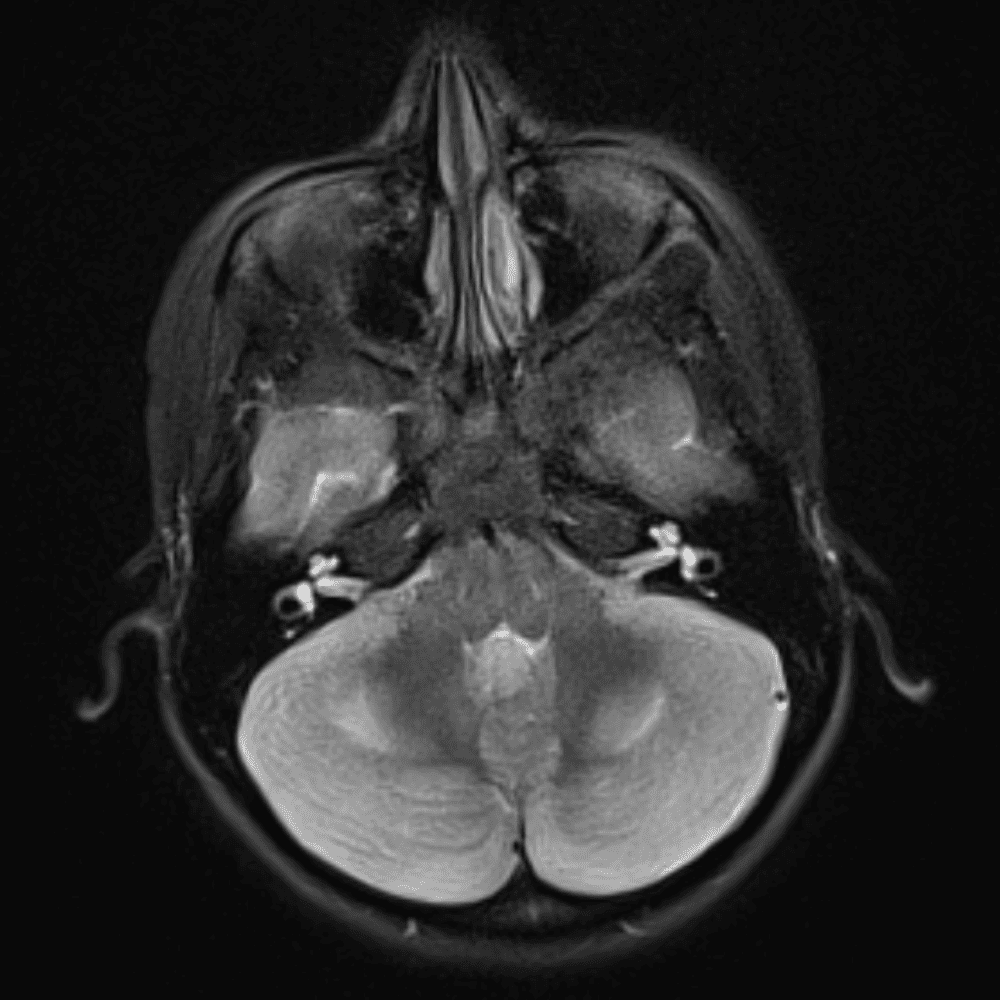

๋‹น์ง ์‹œ ํ”ํžˆ ๋ณผ ์ˆ˜ ์žˆ๋Š” ์‚ฌ๋ก€์˜ ์ „ํ˜•์ ์ธ ์˜ˆ๋ฅผ ํฌํ•จํ•ฉ๋‹ˆ๋‹ค.

39 ์‚ฌ๋ก€

์—ฐ์Šต

๋ฏธ๋ฌ˜ํ•˜๊ฑฐ๋‚˜ ์–ด๋ ค์šด ์‚ฌ๋ก€์™€ ์ผ๋ถ€ ์ •์ƒ ์‚ฌ๋ก€๋ฅผ ํฌํ•จํ•˜์—ฌ ๋‹น์ง์„ ์‹œ๋ฎฌ๋ ˆ์ด์…˜ํ•ฉ๋‹ˆ๋‹ค.

50 ์‚ฌ๋ก€